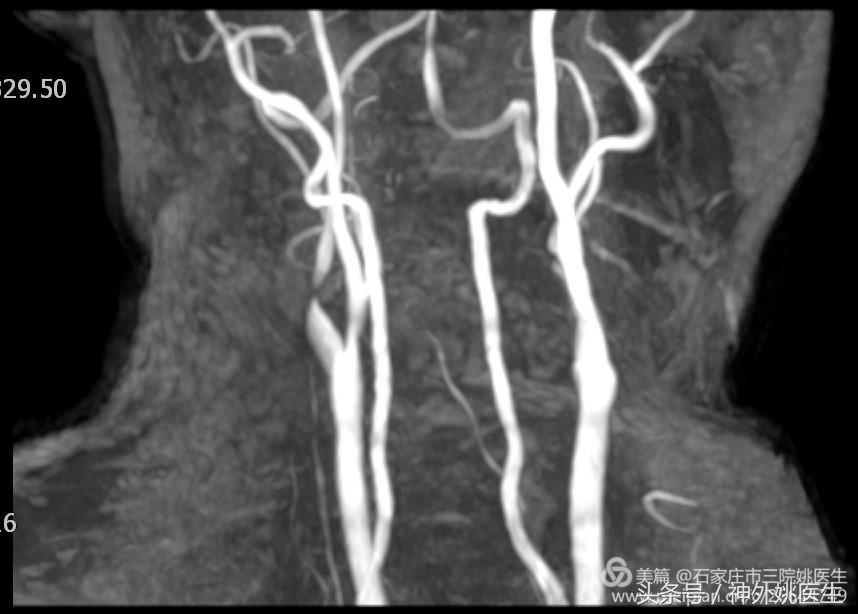

3.颈部MRA:右侧颈内动脉起始部重度狭窄(图3)。

图3